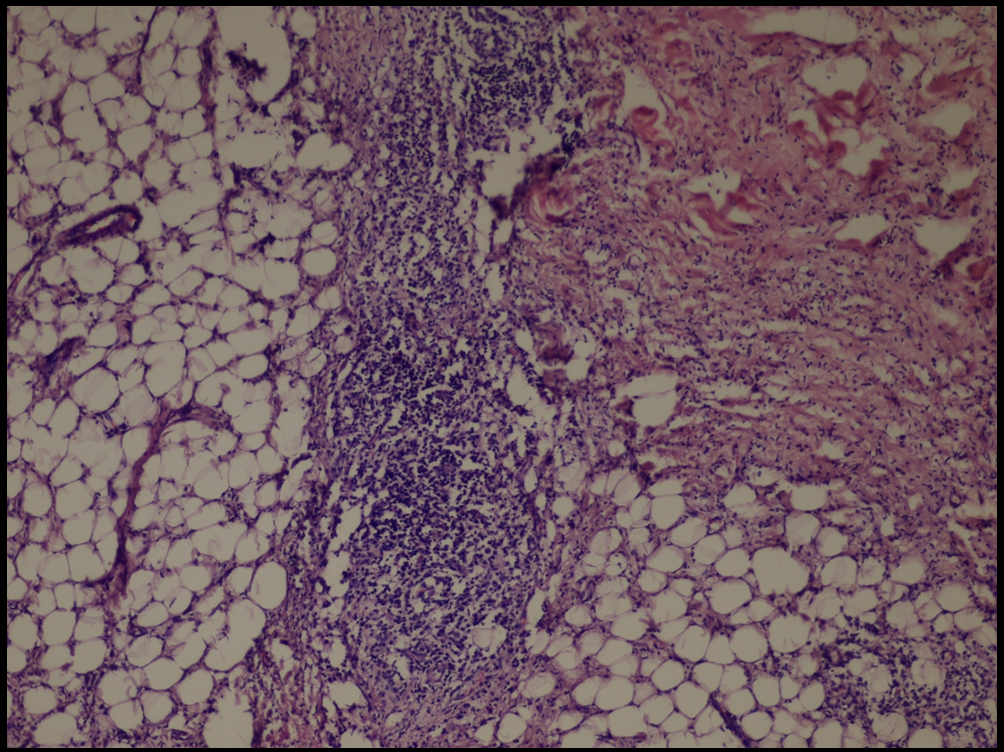

| Fig 7,8 :

The histologic sections of [patient (a), taken by punch

biopsy (4mm) from right thigh] revealed superficial and deep,

intense plasma cellular and lymphocytic infiltrate, primarily

in the lower dermis and fat septae with spillover to the

fat lobules. Fibrosis was present in the deep dermis and

in the fat. There was no vasculitis. (H&E stain; original

magnifications: x 40) |